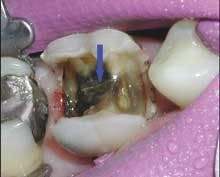

Consider the mush and recurring decay you often find under unbonded amalgams, plus the fractures under weakened cusps or brazenly dead center in sub-amalgam tooth structures. (This is common in baby boomers when canine guidance has been lost.) When I remove an old, defective, amalgam restoration, I recall turning over a rock embedded in the earth and half looking away for fear of finding something scary. Use that simile when recommending replacement of old alloys. It will help you explain the situation (Figures 3 and 4).

When replacing an amalgam that's beginning to fail, you're likely to remove secondary caries and reseal - or in most cases, seal for the first time - the cavo-margin surfaces. You'll often provide shelter and strength for weakened tooth structures by shoeing areas with composite or placing indirect restorations such as crowns or onlays (Figures 5-8).

If you intercept a fracture or secondary caries tracking for pulp-central, you can save your patient the cost and pleasures of root canal therapy or worse - extraction. Once they understand, patients appreciate preventive intervention (Figures 9 and 10).